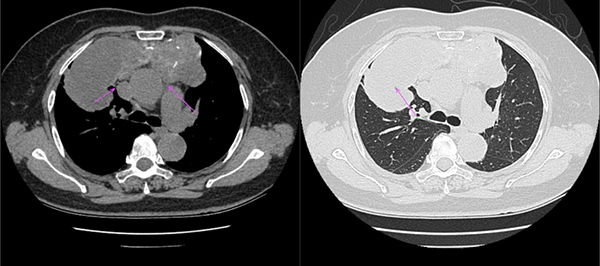

图:侯阿姨的CT片,肿物主要位于右侧纵隔,波及左侧,压迫右肺上叶(右图长箭头),但与上腔静脉(短箭头)和主动脉(长箭头)界限清晰

对于侯阿姨的病情,刘志东主任根据CT检查做出了精确的判断:“虽然这个患者肿物比之前老康的更大,但与周围组织尤其是主动脉、上腔静脉、心包等界限清楚,并未发生侵袭,右肺上叶主要为压迫性肺不张,整体手术难度低于老康。”在刘志东主任的带领下,纵隔外科团队又向纵隔肿物发起了挑战。经术中探查,病变位于前上纵隔,大小约12cm×14cm×10cm,质地较硬,侵及右肺上叶,且右肺上叶部分肺出现肺不张、肺实变。在此情况下,刘志东主任团队仅用30分钟,就完成了纵隔肿瘤的切除,纵隔外科团队再次创造了奇迹。